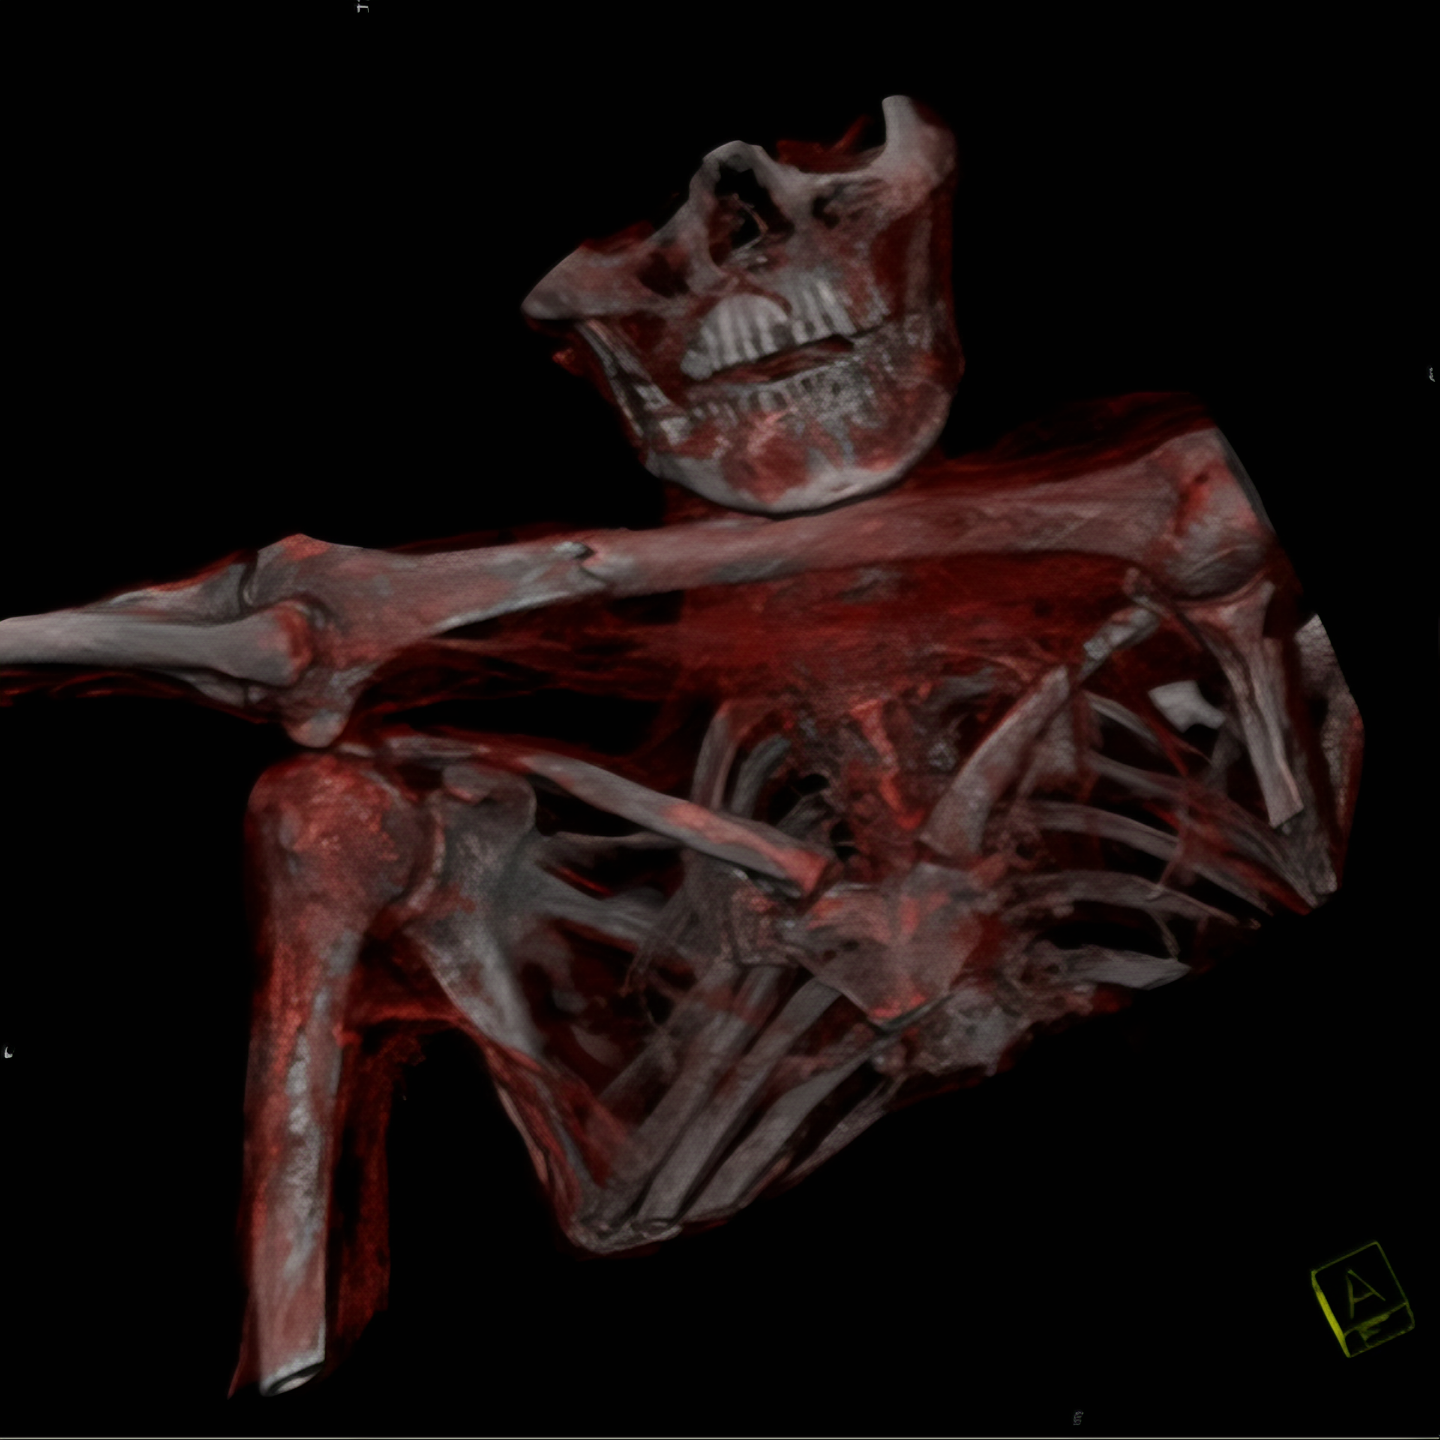

외치에 대한 CT 검사에서는 수상 한 부분이 더 두드러졌다.

그의 왼쪽 견갑골 부분에서 2 센티 정도 폭의 구멍이 발견된 것.

이 구멍은 그의 왼쪽 폐 언저리까지 뻗어 있었다.

우선 외치에 대한 신체검사가 재개되었는데 이 과정에서 병리학자인 Eduard Egarter Vigl은 외치 어깨 부분 피부에서 매우 수상한 피부 손상을 발견했다.

CT로 찾은 외치 어깨 부분 구멍은 이 피부 손상 부분에서 시작된 것은 분명해 보였다.

이 피부를 뚫고 들어간 무엇인가가 외치 영감님 몸 안으로 파고 들어간 것이다.

이 조사에서 확인 된 것은, 외치의 몸안에 남아 있는 것은 돌로 만든 화살촉.

아마도 그는 죽기 전 누군가가 쏜 화살에 맞았을 터인데 그 뚫고 들어간 양상을 보면 왼쪽어깨 빗장밑동맥 (subclavian artery)을 건드렸을 것이다.

결과적으로 이 정도 큰 크기 혈관이 손상을 보면 막대한 출혈로 쇼크에 빠질 수밖에 없었을 것이니

외치가 죽은 원인은 바로 화살에 의한 외상사였을 가능성이 매우 높아진 셈이다.